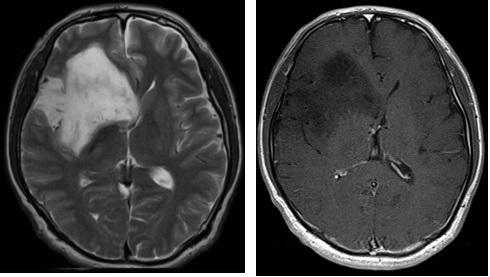

脳を構成する細胞の中で、神経膠細胞(グリア細胞)と呼ばれる細胞からできる腫瘍の総称です。神経膠細胞の中にも様々な種類があり、種類によって形や成長も異なるため、病理学的分類も非常に複雑です。脳に発生する腫瘍の中でも頻度が高く全脳腫瘍中の約1/3を占めます。原発性脳腫瘍は腫瘍の形態学、細胞学、分子遺伝学、免疫組織学的特徴を併せて評価するWHO分類と呼ばれる分類法が広く普及し、治療手段の選択と成績を表す指標となっています。神経膠腫の場合、予後の良好な方から不良の方へグレード1〜4に分類され、神経膠腫グレード2は低悪制度、3と4を悪性神経膠腫と総称しています。グレード1は小児発生が多いのに比べ成人ではグレード2,3,4の発生が主であり、いずれも脳内に浸潤性に発育するとされています。

頭痛・片麻痺・失語・意識障害・痙攣発作など腫瘍が発生する部位に応じた症状が見られます。グレード1,2は症状がゆっくり進行しますが、グレード3,4の悪性度の高い腫瘍では症状が急速に進行します。神経膠腫の10%程度に脳内出血を伴うため、脳卒中との鑑別が難しい場合があります。脳ドックなどで偶然見つかることもあります。脳は前頭葉・側頭葉・頭頂葉・後頭葉・脳幹・小脳など、部位によって様々な機能を持っていますので、脳腫瘍が頭蓋内のどこに発生するかによって様々な症状をおこします。

グレード2:この腫瘍は比較的ゆっくり成長する腫瘍であるために、条件に応じて治療法が変化します。グレード4と比較して5年生存率70%以上ですが、10年生存するのは半数程度、20年生存できるのは全体の1/5程度です。現在の推奨される治療は、40歳未満かつ手術でほぼ摘出が達成された場合には何もせずに経過観察、これら条件を満たさない場合には遺伝子の変異を考慮して放射線単独、化学療法単独、放射線+化学療法のいずれかが選択されます。腫瘍が小さい場合や完全に摘出された場合でも必ず定期的にMRIを行い経過観察することが必要です。